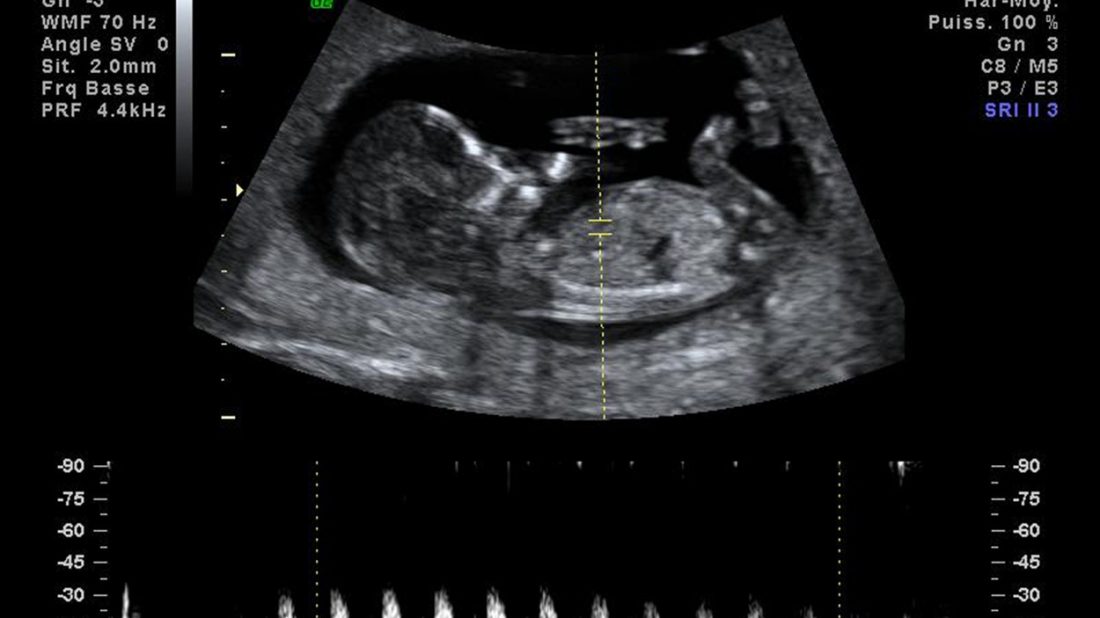

VÁŠ DOTAZ Jsem v 15. týdnu těhotenství a dnes jsem byla v poradně. Paní doktorka mi udělala běžné vyšetření pak kontrolovala ozvy a nic. Snažila se mě uklidnit, že mám širokou pánev a zapadlou dělohu. Příští týden jdu na odběry, tak prý ty ozvy překontroluje. Je to v pořádku? Helena